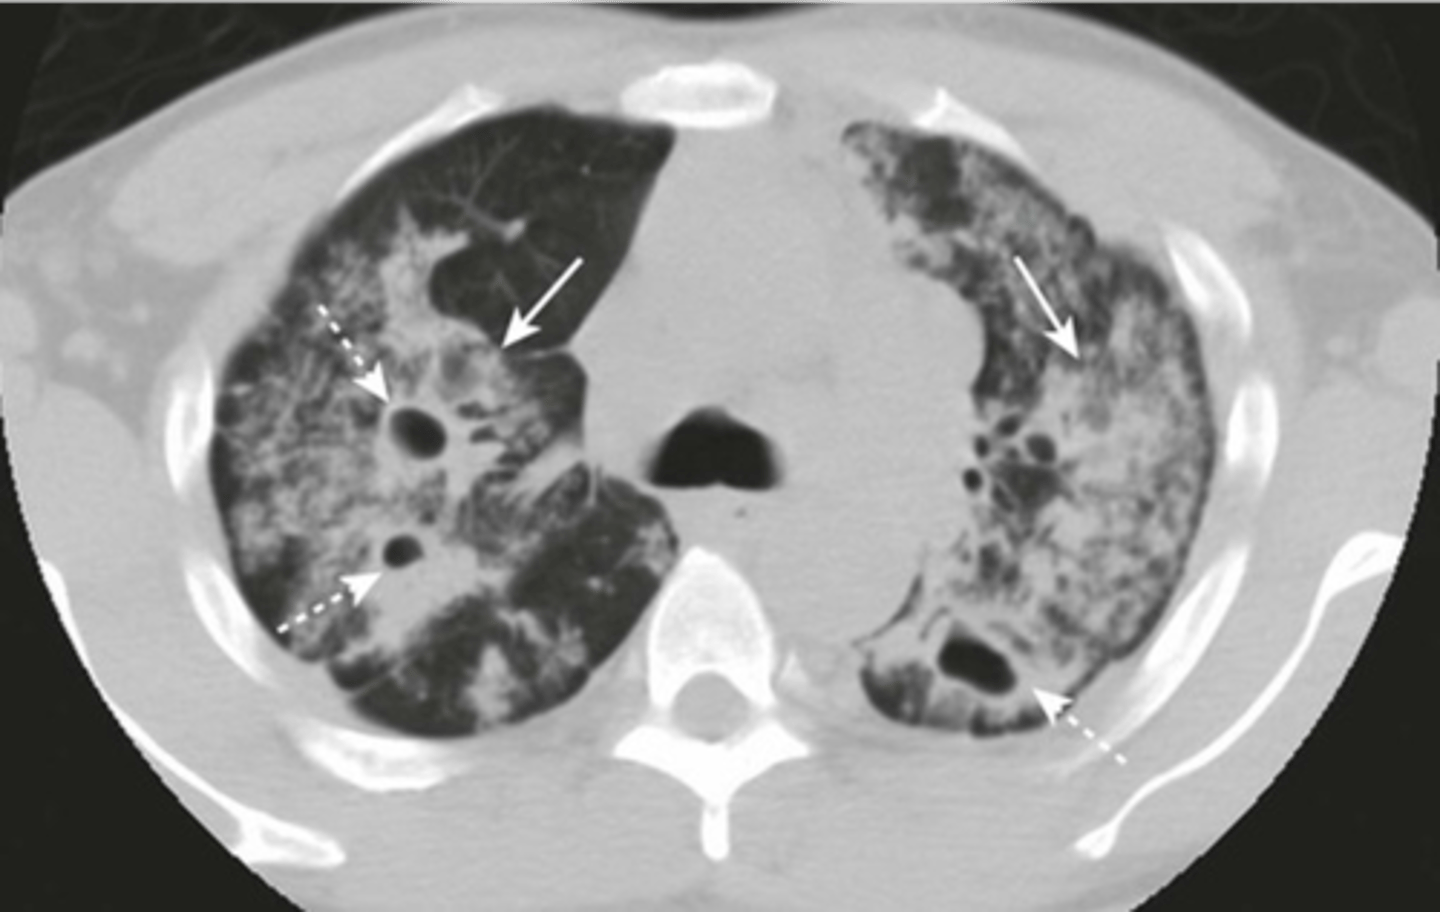

-parallel line opacities (tram tracks)

-signet ring signs

-thickened walls of dilated bronchi

-cystic lesions

bronchiectasis appearance